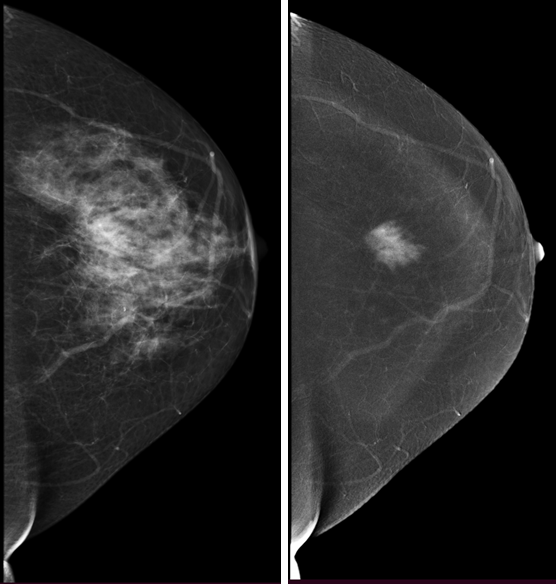

Контрастная спектральная маммография (КСМГ) – инновационный метод диагностики. При выполнении КСМГ вам введут контрастное вещество на основе йода – это позволит врачу увидеть патологические изменения, которые его накапливают. Возможности выявления рака молочной

Но следует помнить, что на йодсодержащие контрастные вещества может быть аллергическая реакция, также они противопоказаны пациентам с патологией почек и печени.

КСМГ может в определенных случаях быть альтернативой МРТ, например, при невозможности выполнить МРТ молочных желез.

Рис.4 Маммограмма с контрастом: фиброаденома молочной железы

Рис.5 Маммограмма с контрастом: рак молочной железы